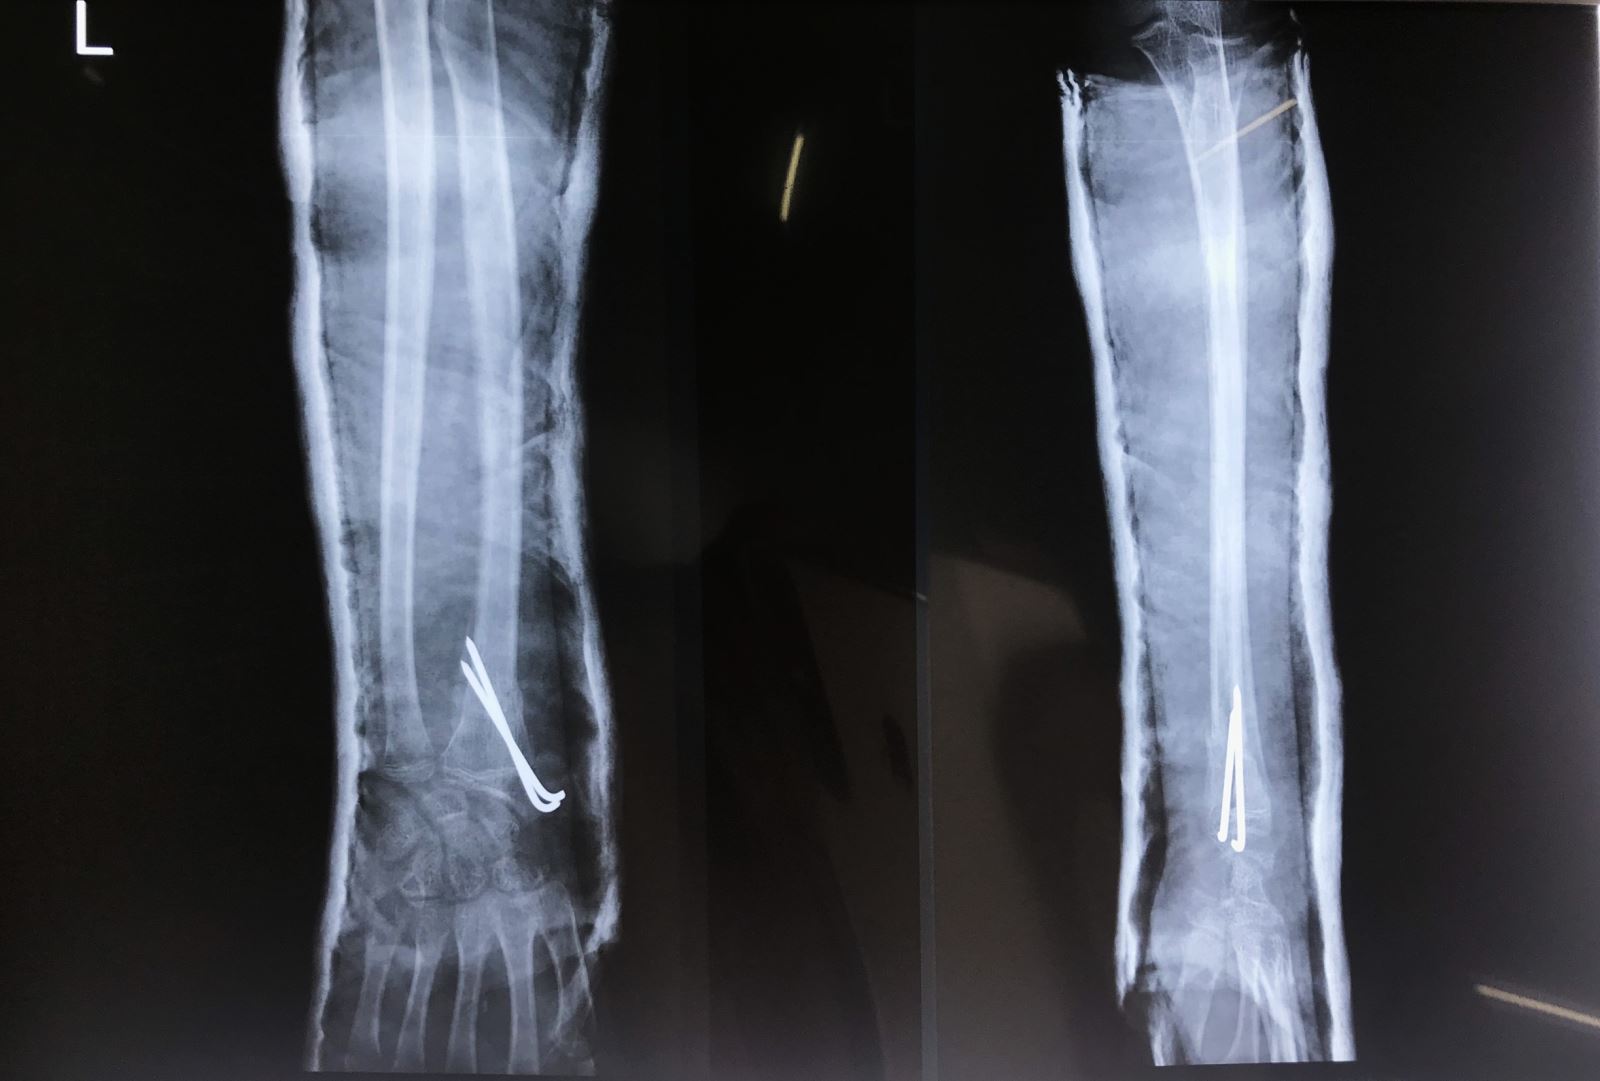

- Nắn kín và xuyên đinh qua da dưới màn hình tăng sáng

- Mổ hở nắn chỉnh và cố định bên trong: Nắn kín thất bại